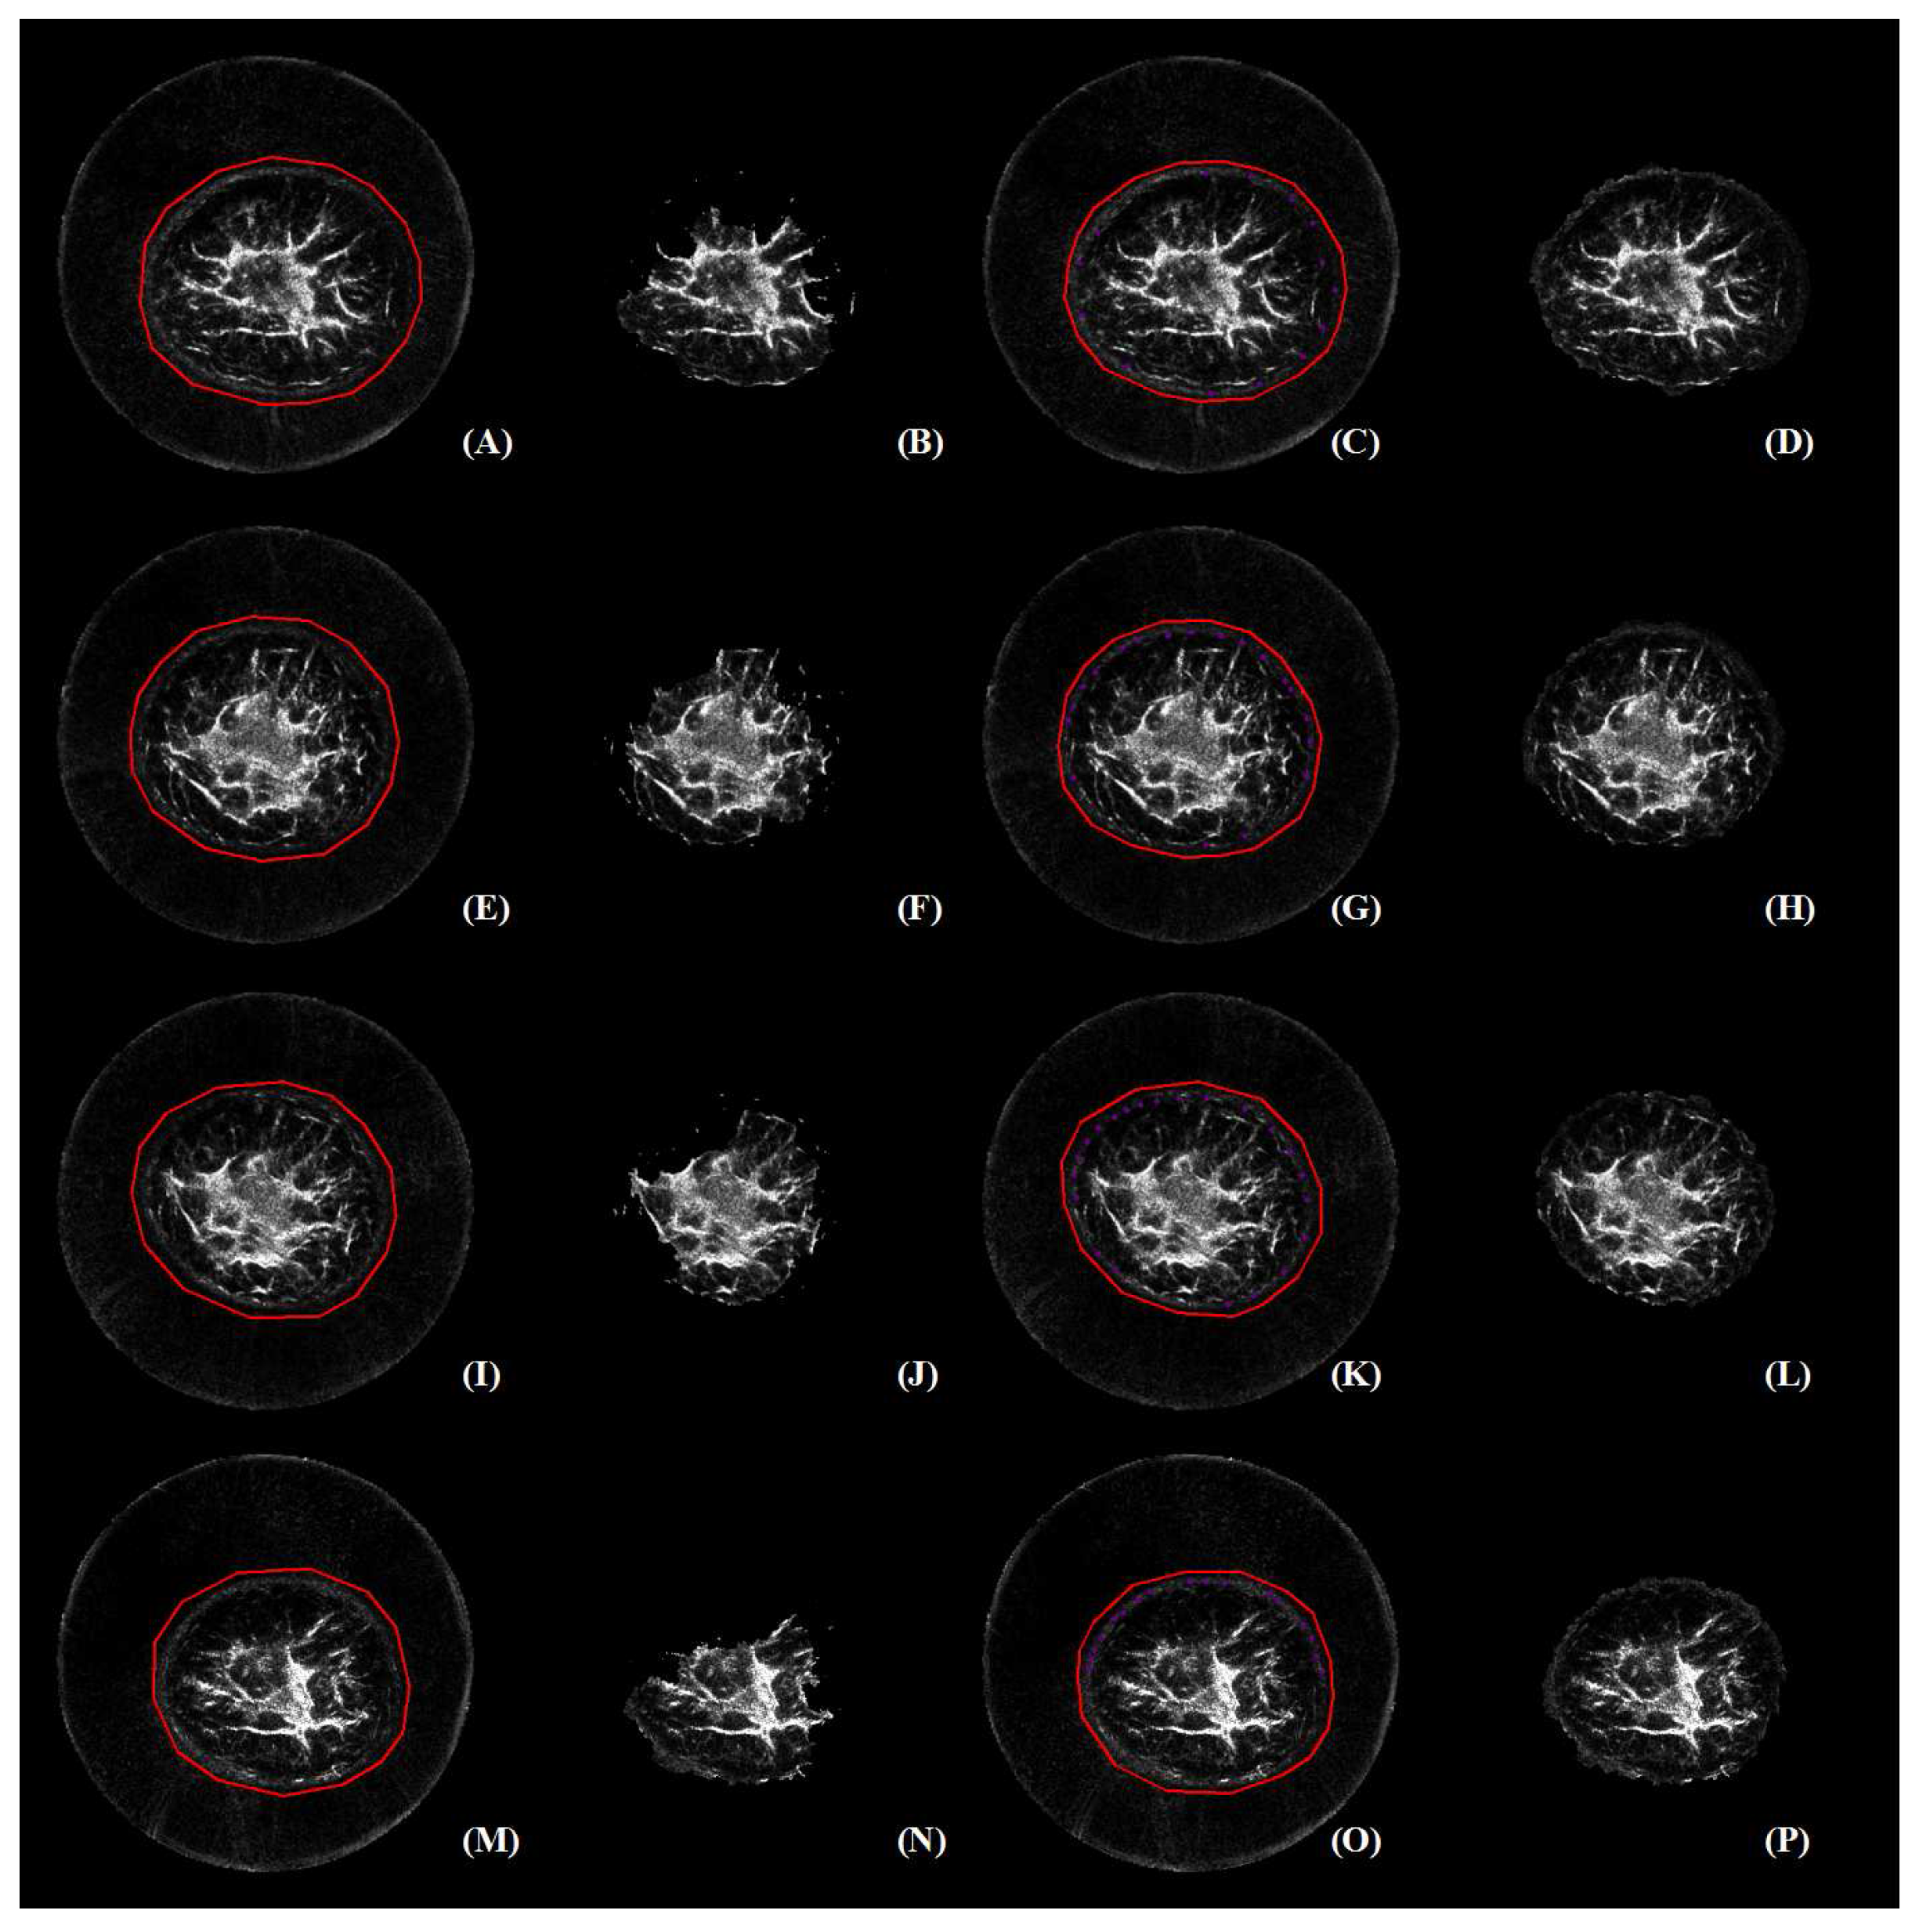

3.2. Perceived Evaluation

3.3. Quantitative Comparison